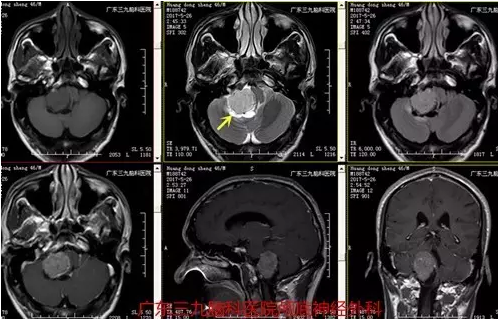

图2:术前磁共振提示肿瘤位置、大小约95px×87.5px×112.5px

非典型脉络丛乳突状瘤在颅脑MRI上呈T1等或稍低信号,T2高或等信号,多为囊实性改变,不同程度强化,CT呈稍高密度,瘤内多见钙化影,应与脑膜瘤及听神经瘤相鉴别,本例MR为囊实性改变,其实性部分较大,增强后呈欠均匀明显异常强化,囊性部分位于周缘,边界部分欠清,大小约为95px×87.5px×112.5px,CT呈稍高密度影为主。基本符合病变特征。